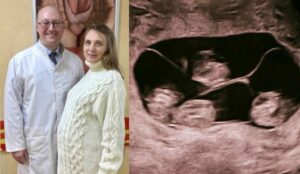

Earlier this week, a woman—whose identity is being kept private as she recovers—gave birth to four identical baby girls. While quadruplets are rare enough, the fact that these sisters are identical makes them a medical phenomenon.

Unlike fraternal quadruplets, which occur when four separate eggs are fertilized, identical quadruplets happen when a single fertilized egg splits into two, and then those two split again. It is a biological fluke of nature that creates four humans with the exact same genetic blueprint.

The birth of identical quadruplets is what scientists call a monozygotic event. Because they come from the same egg, they share 100% of their DNA.

The “Split”: For this to happen, the egg must split within the first few days of fertilization. If it splits too late, there is a risk of conjoined twins; however, in this case, the splits occurred perfectly, allowing four separate umbilical cords and sacs to develop.